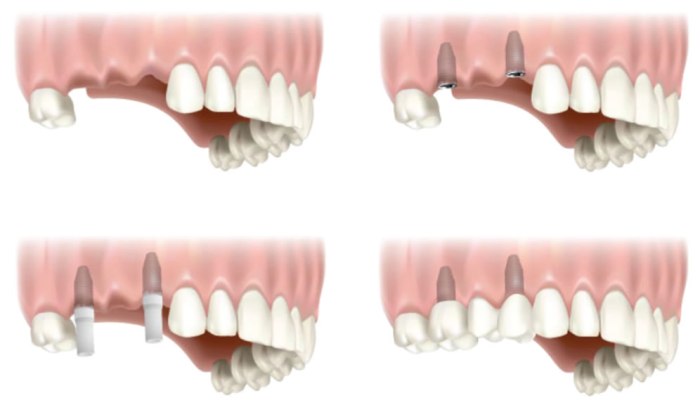

4. Quy trình cấy ghép Implant

Bước 4: Tiến hành cấy ghép implant tại phòng khám vô trùng và hiện đại

Sau khi đặt trụ implant bác sĩ sẽ tiến hành phục hình răng sứ từ 3-6 tháng sau đó theo kế hoạch đã đề ra.

5. Một số hình ảnh cấy ghép Implant

Mất răng cửa và phục hình bằng Implant

Mất răng cửa và phục hình bằng Implant

Mất hai răng và phục hình với Implant

Mất hai răng và phục hình với Implant

Mất nhiều răng và phục hình với Implant

Mất nhiều răng và phục hình với Implant

Mất toàn bộ răng và phục hình với sự nâng đỡ 4 Implant

Mất toàn bộ răng và phục hình với sự nâng đỡ 4 Implant